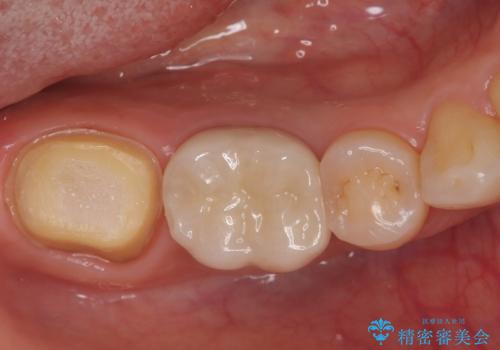

ズキズキ痛い歯 オールセラミッククラウンによる修復

- 冷たいもので長引く痛みがあることを主訴に来院されました。

抜髄を行い、オールセラミッククラウンにて修復を行いました。

根管充填はバイオセラミックシーラーを使用しています。